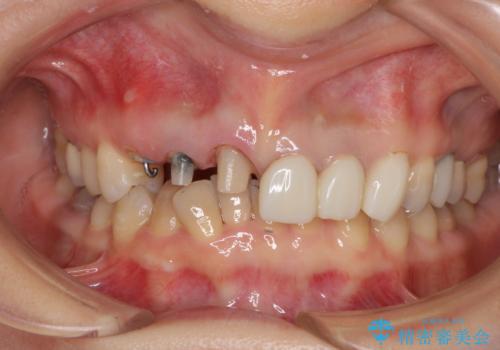

- 前歯のセラミッククラウンの不自然な色調と、虫歯を気にして来院された患者様です。

6歯全てが連結されていたため、外れかけていた右の犬歯は知らぬ間に虫歯が深くにまで進行していました。

深い虫歯の犬歯は、根管治療を行った後に部分矯正を行い、歯周外科処置により環境を整えてから、6歯それぞれのオールセラミッククラウンにて補綴することとしました。